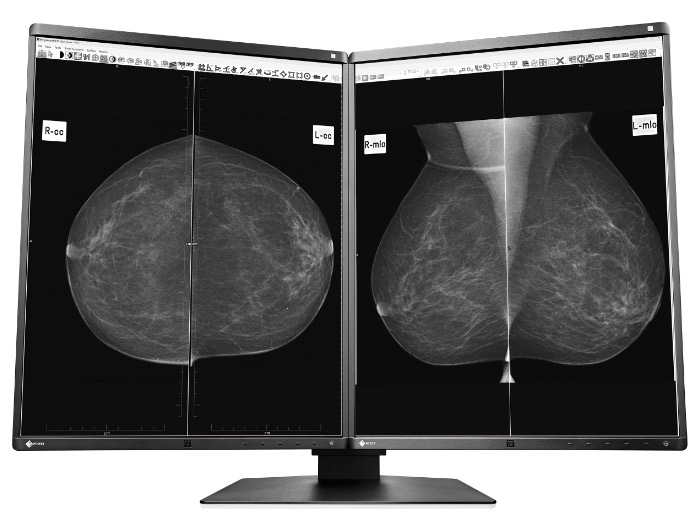

Nas configurações Single (Um monitor) ou Dual (Dois monitores), o GX560 é o produto mais sofisticado da categoria para produção de laudos de Mamografia Digital e Tomossíntese. Equipado com tecnologia embarcada EIZO de Controle de Qualidade – RADICS – o monitor é mantido no padrão DICOM Part 14 ao longo de sua vida útil.

Nas configurações Single (Um monitor) ou Dual (Dois monitores), o GX560 é o produto mais sofisticado da categoria para produção de laudos de Mamografia Digital e Tomossíntese. Equipado com tecnologia embarcada EIZO de Controle de Qualidade – RADICS – o monitor é mantido no padrão DICOM Part 14 ao longo de sua vida útil.